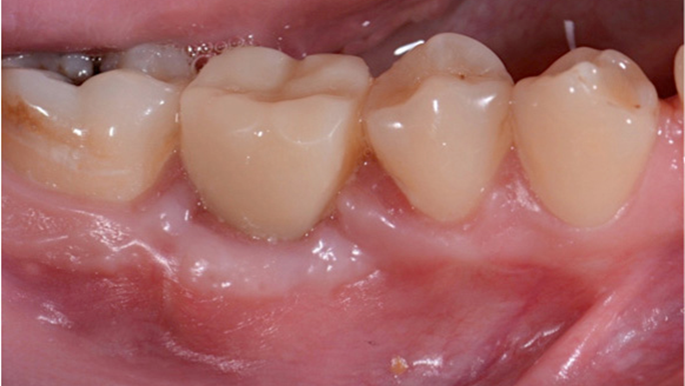

Clinical case: # 46 implant placement & GBR using i-Gen membrane for significant vertical resorption & mixed bone defect

AnyRidge, mandibular posterior, i-Gen, resorption, bone defect, bone regeneration, space management, #46, GBR, Dr. Iulian Filipov

“AnyRidge KnifeThread achieves excellent stability in regenerated bone & even in only 3mm bone height!”